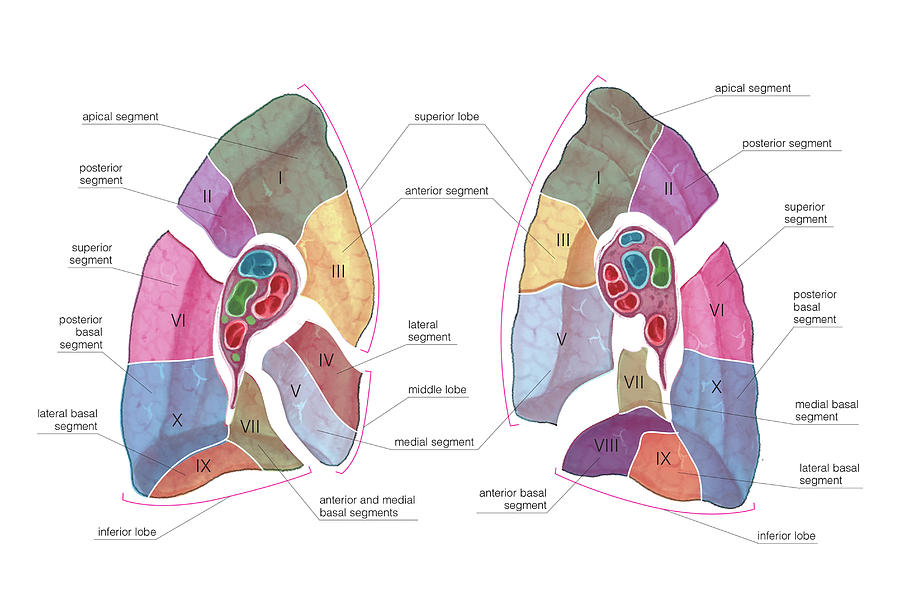

Анатомические изображения сегментов легких различных животных

Раздел: Другие животные